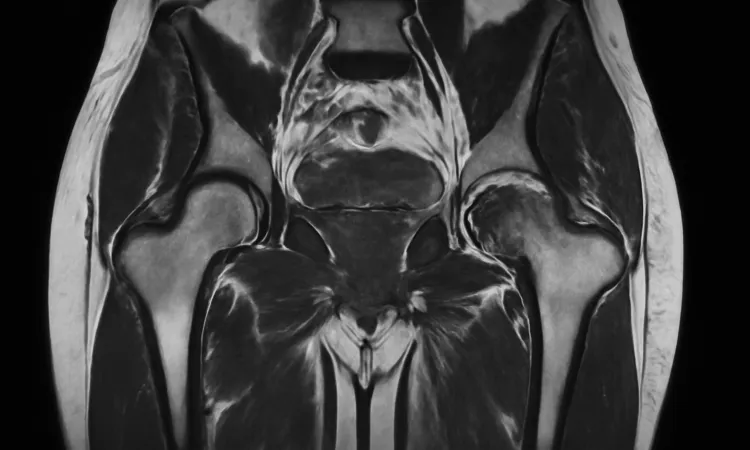

МРТ тазобедренного сустава — это один из наиболее эффективных методов диагностики коксартроза, позволяющий получить четкое изображение внутренних структур и оценить степень повреждений. Точные данные, полученные на этом этапе, важны для правильного выбора лечения и профилактики последующих осложнений.

Одним из ключевых методов является МРТ тазобедренного сустава. Это исследование позволяет получить высококачественное изображение мягких тканей, хрящей и костей, что необходимо для оценки состояния сустава. На МРТ можно увидеть изменения, характерные для коксартроза, такие как истончение хрящевой ткани и наличие остеофитов.